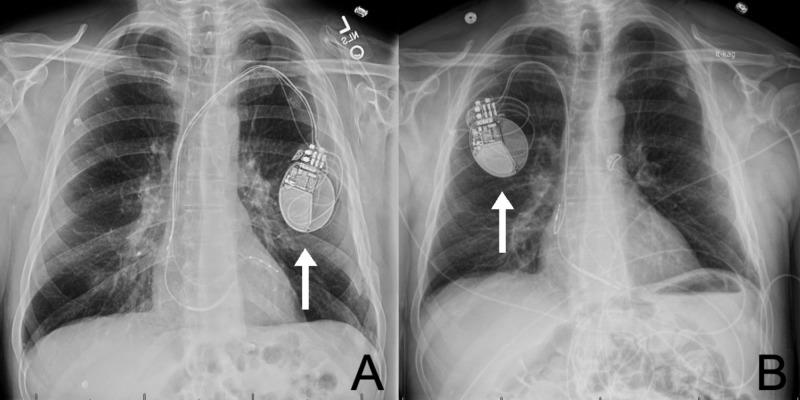

Erosive Twiddler's Syndrome: A Severe Case with Externalization of the Pacemaker.

Implantable pacemakers have been the mainstay of therapy for patients with severely decreased left ventricular ejection fractions and recurrent arrhythmias, among other cardiac pathology. Twiddler's syndrome (TS) is an uncommon but potentially life-threatening complication of pacemaker therapy, defined as pacemaker malfunction in the setting of device lead dislodgment due to physical manipulation. Traditionally, there are three distinct TS variants (reeling, ratchet and coiling). This case offers evidence of a unique and new variant of TS, severe recurrent erosive subtype with pacemaker externalization.